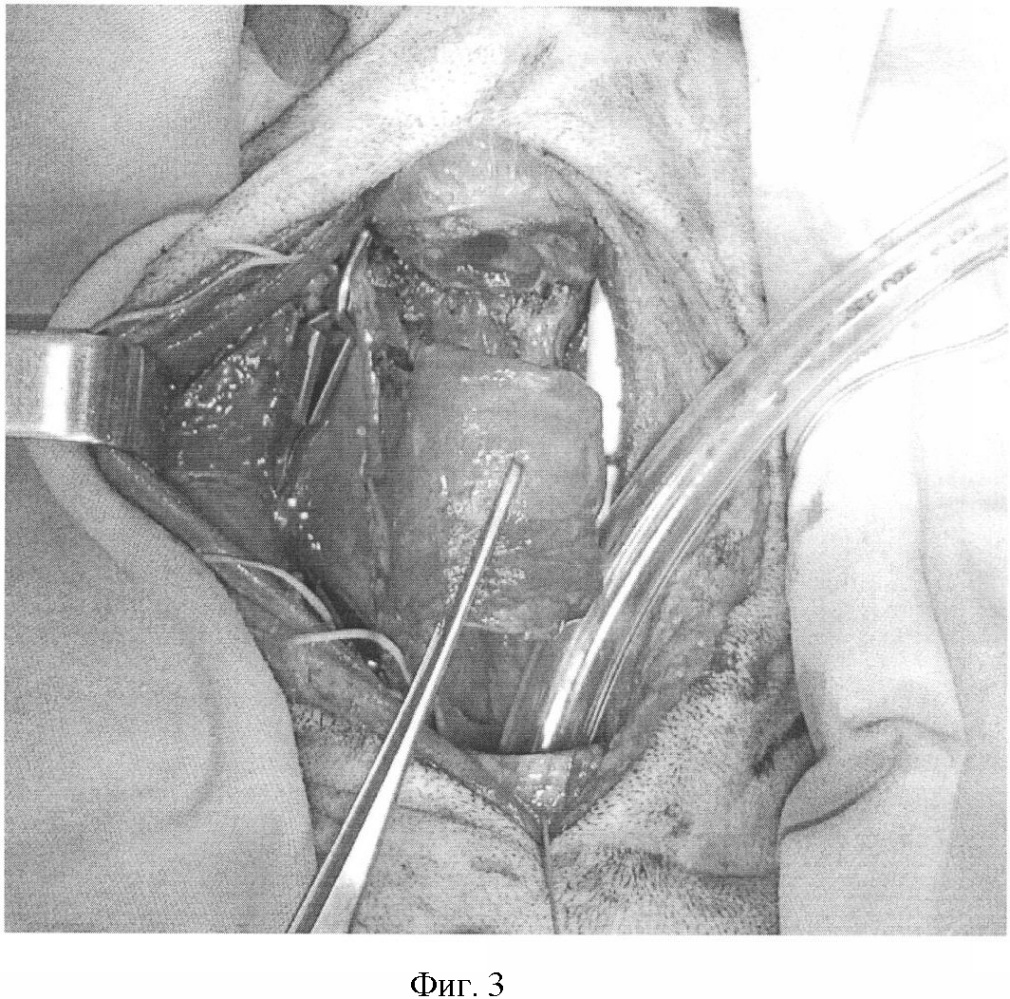

Фиг.3. Пересечена трахея на уровне перстнетрахеальной мембраны и между 8 и 9 хрящевыми полукольцами.